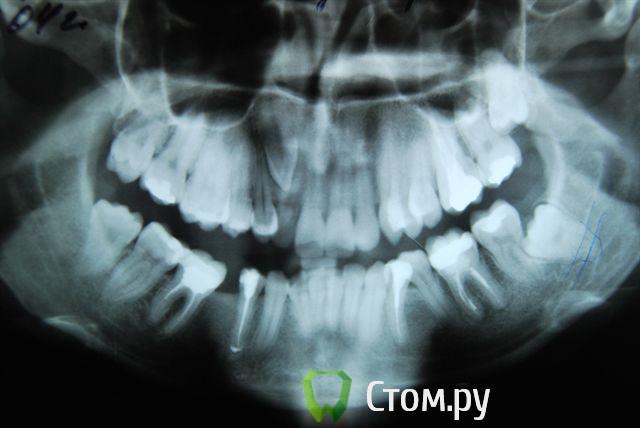

Александрстрад Опубликовано 8 ноября, 2011 Поделиться Опубликовано 8 ноября, 2011 Уважаемые доктора! Потерял и веру и надежду в возможность решения проблемы у своей жены. Одел на нее брекеты у знакомых ортодонтов в Москве, результаты, которых видел. В процессе лечения консультировался и ЦНИИСЕ у Арсениной и у других докторов, работал в крупнейшей медицинской компании, доступ к врачебной базе был очень большой. В процессе лечения все говорили что лечение идет нормально, а когда сняли брекеты ужаснулись все. Хронология лечения у ортодонта описана ниже, включая проблемы, которые мы получили после лечения.1. Показания к лечению брекет-системамиХруст при жевании в правом суставе.Замещение отсутствующего на нижней челюсти пятого зуба справа в течение 10 лет. В результате отсутствия 5-го зуба: наклон 4-го и 6-го по направлению друг к другу, резорбция (убыль) костной ткани на челюсти на месте отсутствующего зуба.Левый клык на верхней челюсти выходил из зубного ряда.Смешение центра верхней челюсти влево.Правый клык до момента начала лечения на верхней челюсти не вышел, находился в состоянии ретинированного, т.е. не вышел.2. Этапы леченияНачало лечения брекет системой - 2006 год.Снятие брекет системы 2009 год.Что было сделано:1. Левый клык на верхней челюсти был поставлен в зубной ряд.2. По отсутствующему 5-му зубу на нижней челюсти - доктор принял решение по замещению, путем передвижения зубов на нижней челюсти вправо,что и было проделано.3. Через 2 года ношения брекет-системы было принято решение по вытаскиванию левого ретинированного клыка.Был удален 3-ий зуб и в освободившееся пространство был вытянут клык.В результате данного объема работ и некорректной работы доктора,были завалены внутрь зубы на верхней челюсти - левая сторона, начиная от 1-го и далее, от резцов до жевательных.Также после сделанного панорамного снимка выяснилось, что произошло рассасывание корней 4-х фронтальных зубов на верхней челюсти более 65%.4. Также в процессе лечения был потерян 6-ой зуб на нижней челюсти слева. Проблемы сейчас1. Хруст в челюсти при жевании и зевании не прекратился, а появился и слева.2. Заваленная левая часть зубов на верхней челюсти не позволяет смещать нижнюю челюсть влево,тем самым перегружаются жевательные мышцы справа, в результате бывают головные боли и боли в мышце при жевании.3. Рассасывание 4-х верхних зубов.4. Расстояние справа между верхней и нижней челюстью на данные момент 3 мм. Сделали после снятия бректов исселдование у ортопеда, заключение ниже. Ее приговор - ТОТАЛЬНОЕ протезирование.Жене 36 лет, она даже слышать об этом не хочет. ПОМОГИТЕ РЕШИТЬ ПРОБЛЕМУ, НАДЕЖДЫ БОЛЬШЕ НЕТ. Заключение ОРТОПЕДАTreatment objectives∙ Transversal and sagittal discrepancy- make passive centic arch of upper jaw fit to active centric active lower jaw∙ First interference contact in RP on 24-34 and 37-27 with disocclusion for + 2 mm. Rp= 0=-2 mm, and till last contact =-4mm on incisal pin, so increase IP for =+3mm∙ Muscle problems∙ Change OPI on right side from 15 degrees to 20 degreees and change Cui right side to∙ Increse LFH +3 mm on incisal pin∙ Curve of Spee will be accentuated for 36∙ Steep condyle- decreased radius curve of Spee∙ Cui for 13 is not more than 55 degrees∙ Curve of Spee=Curve of wilson for 36 and 46∙ Rotation of mesial cusp of 6 down- change OPI for 36 – rotate 36 with mesial contact point OPI 6 = 35 degrees for DOA=12 degrees Ссылка на комментарий

Премоляр Опубликовано 9 ноября, 2011 Поделиться Опубликовано 9 ноября, 2011 Непонятны причины такой резорбции корней резцов...Да,задача номер один-стабилизация ВНЧС. Я бы пока не думал о повторном ортодонт.лечении,учитывая степень резорбции корней. Ссылка на комментарий

Александрстрад Опубликовано 10 ноября, 2011 Автор Поделиться Опубликовано 10 ноября, 2011 Непонятны причины такой резорбции корней резцов...Да,задача номер один-стабилизация ВНЧС. Я бы пока не думал о повторном ортодонт.лечении,учитывая степень резорбции корней. По стабилизации - ортопед начала двигаться в этом направлении, для чего была проведена большая диагностика за 100 000 руб. в артикуляторе, сделаны слепки, снимки челюсти в госпитале МВД (описания делала сама начальник отделения, по отзывам одна из самых квалифицированных в Москве). После чего она вынесла решение по тотальному протезированию для нормализации положения суставов.Если будет возможность посмотреть презентацию с расчетами, которая была сделана и является финальным результатом диагности, готов отправить на почту. Был бы очень признателен.По тотальному протезированию - это катастрофа. Резорбция корней вызвана чрезмерной нагрузкой, в момент вытягивания правого ретинированного клыка. Когда его тянули резинки закрепляли за левую часть верхней челюсти, чтобы инициировать движение клыка, в результате и правую сторону челюсти "завалили" внутрь, а также получили огромную нагрузку на все фронтальные зубы, результатом чего и стала резорбция.Сначала доктор сам не поверил, что это произошло и может произойти в 33 года. Не рассматривался организм в целом при лечении и заболевания, а по факту у жены артрит/артроз. Ссылка на комментарий

Премоляр Опубликовано 10 ноября, 2011 Поделиться Опубликовано 10 ноября, 2011 Господи,какая "каша" из терминов и специалистов у вас...Кто что только не предлагает...Один снял ретейнер,другой приклеит,третий опять лечить будет,четвертый еще 100т возьмет за "диагностику в артикуляторе"... Я считаю что резорбция не связана с перегрузкой из-за опоры,т.к. резорбция наблюдается и на резцах нижней.челюсти. Ретейнер нельзя снимать ПОКА,ибо с такой резорбцией он выполняет роль шины и удерживает зубы. По отдельности без ретейнера могут появиться проблемы(подвижность,тремы и т.д...).Начальным этапом надо "оживить и восстановить" ВНЧС,а не планировать импланты,брекеты и т.д...П.С. Вам необходимо найти грамотного специалиста(гнатолога+ортодонта+ортопеда),а не бегать от одного "профессора" к другому...Это только больше запутает вас...П.П.С. Написал в личку про доктора в Мск Ссылка на комментарий